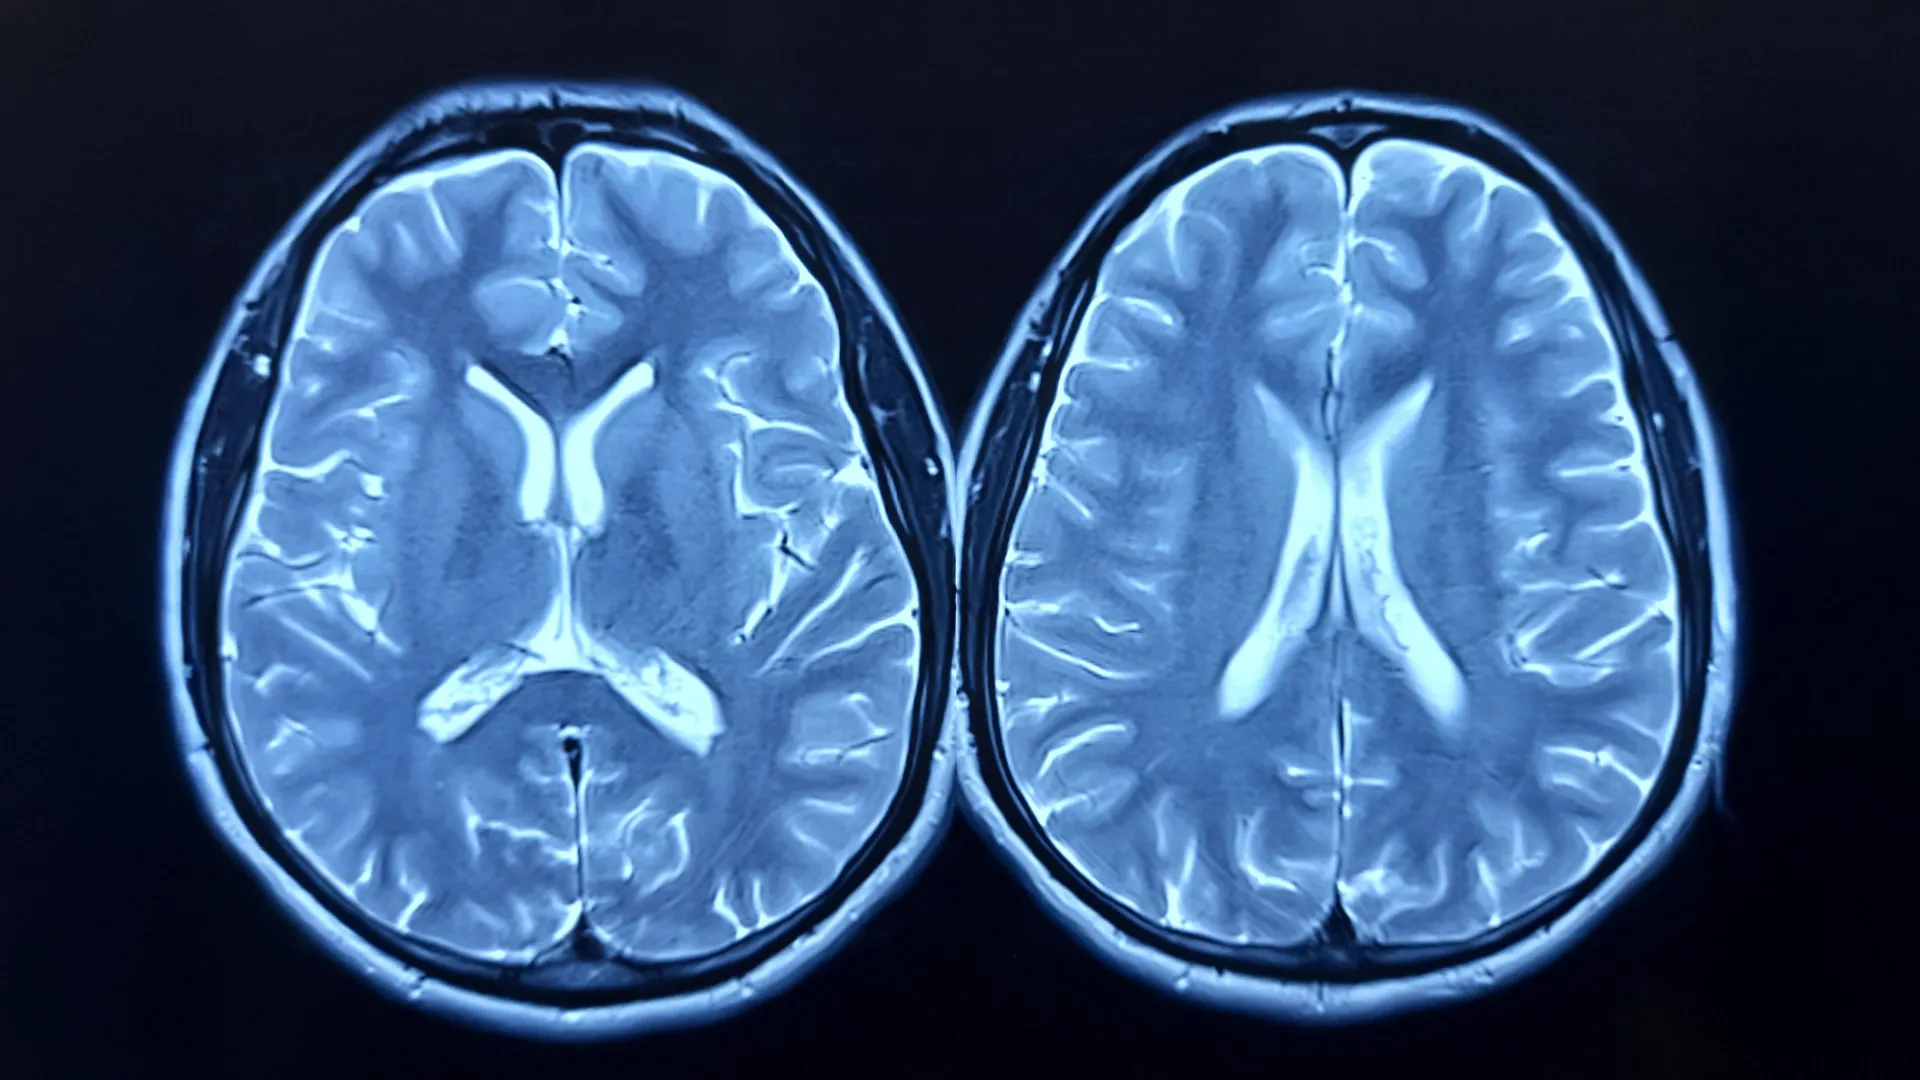

The scientific methodology employed to assess brain age relied on sophisticated Magnetic Resonance Imaging (MRI) technology. This non-invasive imaging technique allows researchers to generate a metric known as "brain age," which is essentially an estimation of how old the brain appears based on its structural characteristics, irrespective of the individual’s chronological age. A disparity between a person’s actual age and their brain’s estimated age, often quantified as brain-predicted age difference (brain-PAD), has been a subject of considerable scientific interest. Prior investigations have established correlations between a higher brain-PAD, indicating an older-appearing brain, and diminished physical and cognitive performance, as well as an elevated mortality risk.

To meticulously track changes, researchers utilized MRI scans to capture detailed structural information of the brain at both the commencement of the study and again after the completion of the 12-month intervention period. Concurrently, cardiorespiratory fitness was assessed through measurements of peak oxygen uptake, commonly referred to as VO2peak, providing a standardized indicator of aerobic capacity.

Upon the conclusion of the year-long trial, a clear divergence in the trajectory of brain aging became apparent between the two study groups. Individuals who actively participated in the exercise program demonstrated a discernible reduction in their brain age. In stark contrast, participants in the control group experienced a slight increase in their brain age. Quantitatively, the exercise group witnessed an average decrease in their brain-PAD of approximately 0.6 years, signifying that their brains presented as biologically younger by that margin. Conversely, the control group’s brains appeared to age by roughly 0.35 years, a change that did not reach statistical significance. When directly compared, the cumulative difference between the two groups approximated one full year, with the exercise group exhibiting the advantage of a younger-appearing brain.